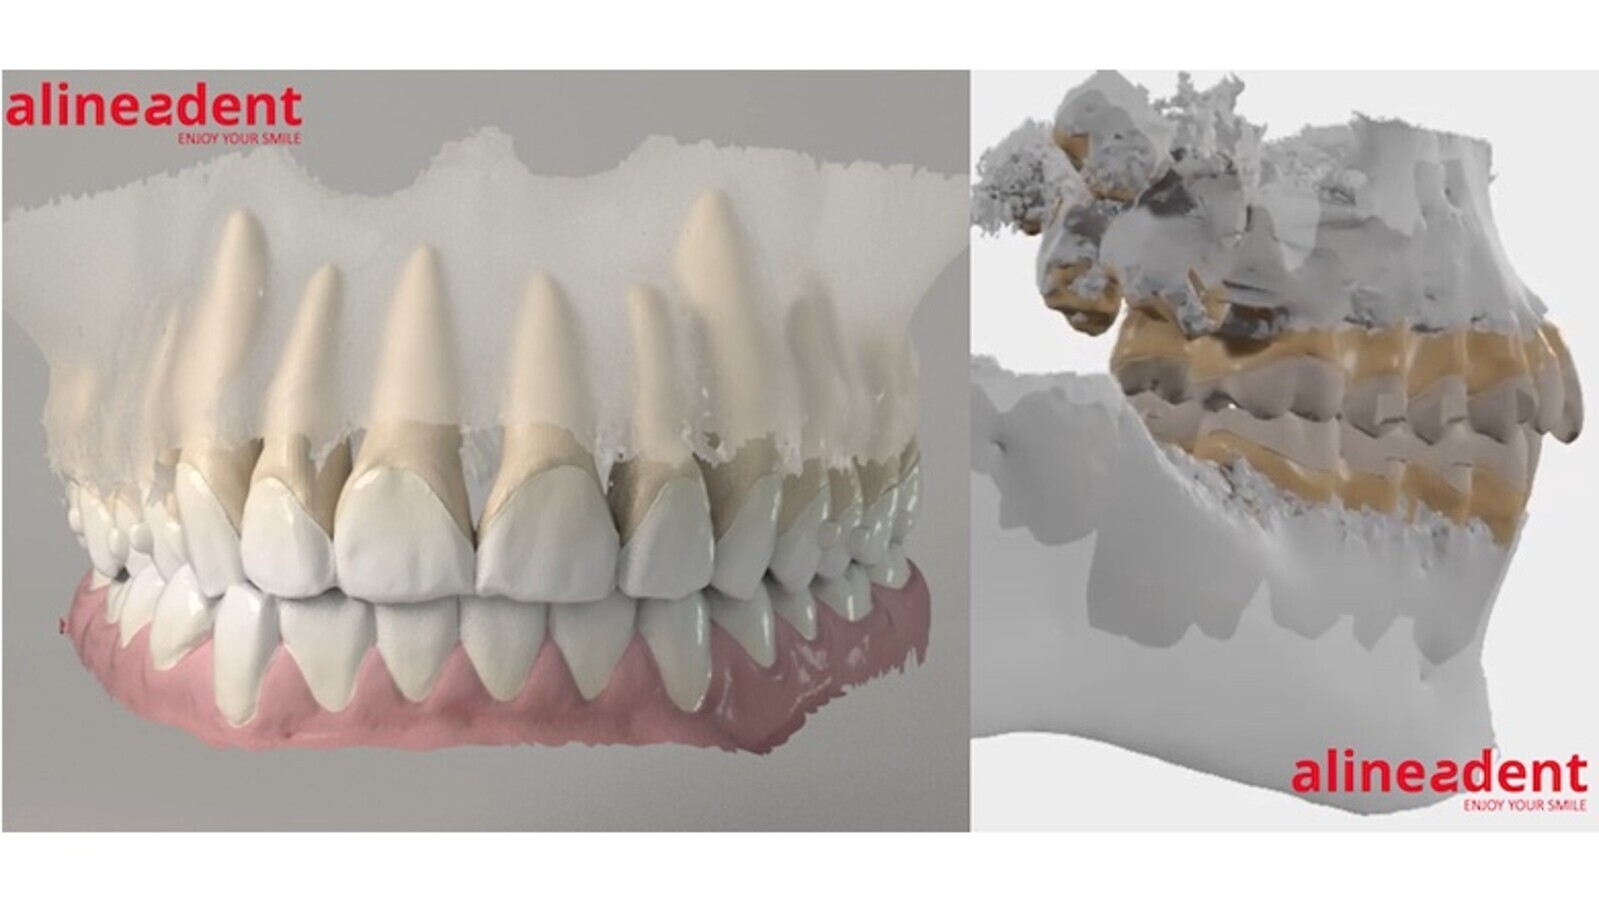

En la figura 14 se pueden ver los ataches más utilizados por nosotros con los alineadores de la compañía española Alineadent, dividiendo estos en pasivos y/o de retención y activos, así como las elevaciones o arcos de torsión y los puntos de presión, los dientes donde se aplican más y una orientación sobre los movimientos dentarios esperados.

Figura 14. Los ataches más utilizados por el autor y los alineadores de la compañía española Alineadent.

La modelización matemática con elementos finitos nos permiten analizar la correlación entre diseño de atache y distribución de fuerzas por la superficie del mismo. El departamento de I+D+I de Alineadent trabaja, en colaboración con la Universidad de Málaga, con los programas de ingeniería más avanzados para optimizar los ataches existentes y desarrollar nuevos diseños más pequeños y eficientes (figura 15).

Figura 15. Nuevos diseños de ataches más pequeños y eficientes desarrollados por Alineadent y la Universidad de Málaga.